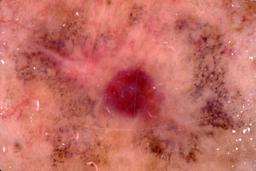

{

"age_approx": 70,

"anatom_site_general": "posterior torso",

"concomitant_biopsy": true,

"dermoscopic_type": "contact non-polarized",

"diagnosis_1": "Malignant",

"diagnosis_2": "Malignant adnexal epithelial proliferations - Follicular",

"diagnosis_3": "Basal cell carcinoma",

"diagnosis_confirm_type": "histopathology",

"image_type": "dermoscopic",

"lesion_id": "IL_3822699",

"melanocytic": false,

"patient_id": "IP_1483425",

"sex": "male"

}